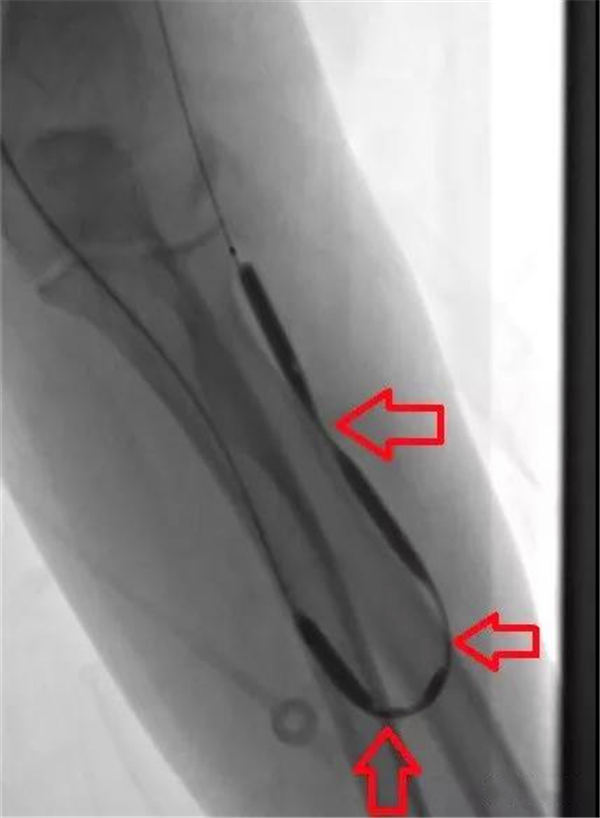

后经球囊扩张内瘘,发现多处血管狭窄,如下图红色箭头所示。